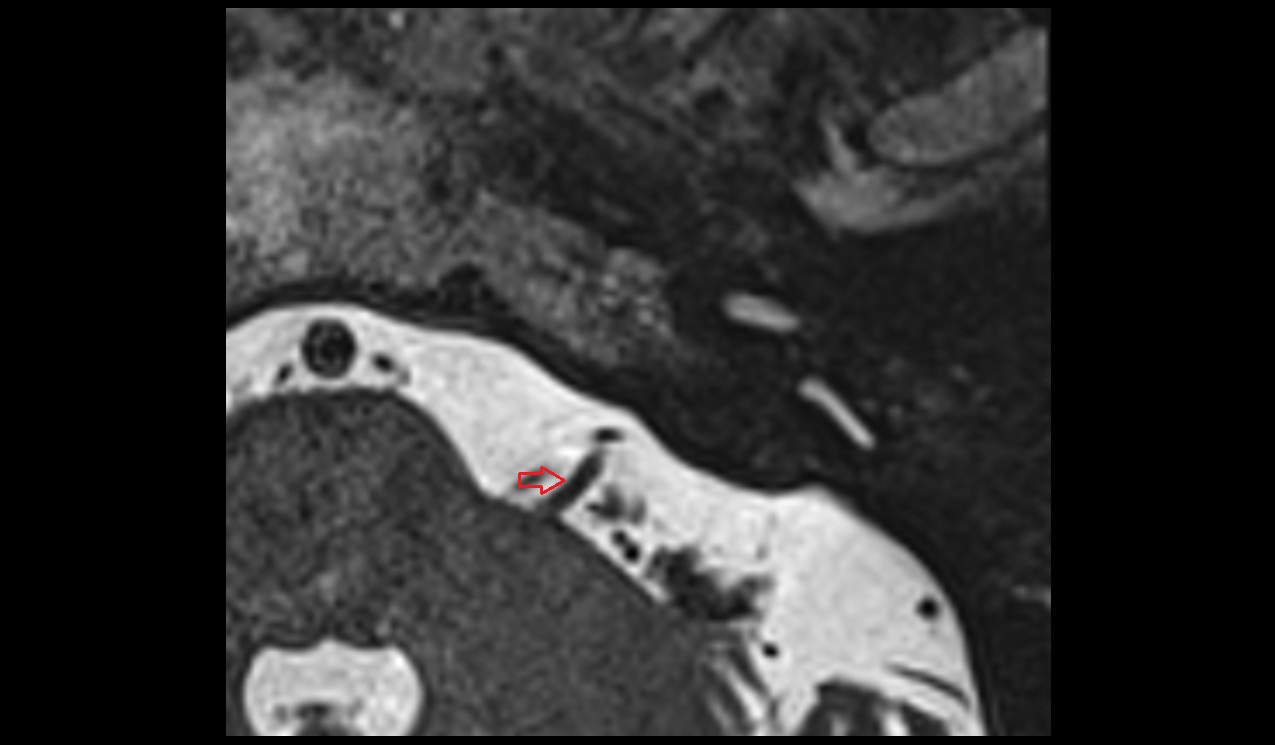

- Mandibular condyle

- Mandibular fossa

- Articular eminence

- Articular surface of mandibular fossa

- Articular tubercle